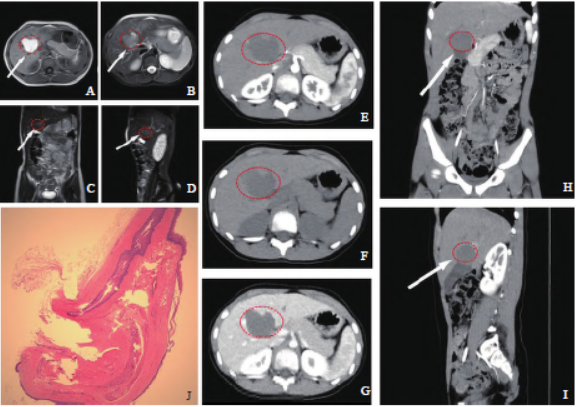

(magnetic resonance imaging,MRI)腹部平扫:各肝叶形态、大小、比例正常,肝左右叶交接区见类圆形占位,大小约32 mm×24 mm×8.4 mm,呈短T1稍长T2信号影。MRI腹部平扫诊断:在肝脏左、右叶交接区(图1A~D),呈类圆形。腹部计算机体层成像血管成像(computed tomography angiography,CTA):肝脏未见增大,左右叶交界区见类圆形占位,大小约34 mm×37 mm×25 mm,边缘光整,增强后该病灶未见明显强化。CTA诊断:肝左右叶交界区类圆形占位,血肿可能(图1E~I)。

图1 患者影像学及病理学表现A~D:MRI平扫示肝左右叶交接区可见一囊性占位(红色圈出),T1加权成像(T1-weighted imaging,T1WI)呈高信号(A),T2加权成像(T2-weighted imaging,T2WI)呈稍高信号(B、C、D),肿块边界清楚。E~I:CT增强扫描。CT平扫

肿块呈偏低密度影(F),增强后动脉期(E、H、I)及静脉期(G)未见明显强化。J:内衬鳞状上皮的纤维囊壁组织,有少量肝组织局部可见于周围(HE染色,×10)。